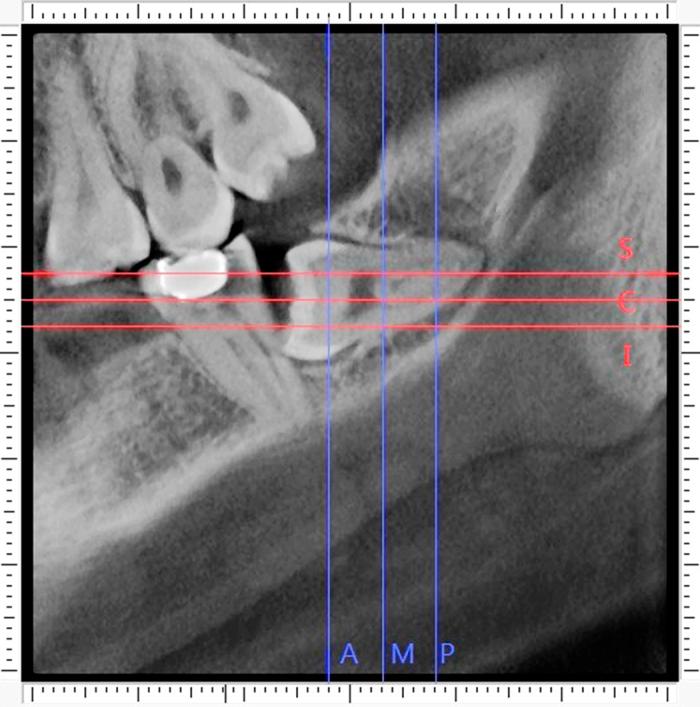

Selecting either buccal or lingual approach for the mandibular third molar surgical extraction has been an intense debate for years. The aim of this observational retrospective study was to classify the molar based on the proximity to the external cortical bone, and analyze the position of inferior alveolar canal (IAC) of each type. Cone-beam CT (CBCT) data of 110 deeply impacted mandibular third molars from 91 consecutive patients were analyzed. A new classification based on the mean deduction value (MD) of buccal-lingual alveolar bone thickness was proposed: MD≥1 mm was classified as buccal position, 1 mm>MD>-1 mm was classified as central position, MD≤-1 mm was classified as lingual position. The study samples were distributed as: buccal position (1.8%) in 2 subjects, central position (10.9%) in 12 and lingual position (87.3%) in 96. Ninety-six molars (87.3%) contacted the IAC. The buccal and inferior IAC course were the most common types in impacted third molar, especially in lingually positioned ones. Our study suggested that amongst deeply impacted mandibular third molars, lingual position occupies the largest proportion, followed by the central, and then the buccal type.

多年来,对于下颌第三磨牙手术拔除选择颊侧或舌侧入路一直存在激烈争论。这项观察性回顾性研究的目的是根据下颌第三磨牙与外侧皮质骨的接近程度对其进行分类,并分析每种类型下颌管(IAC)的位置。分析了91例连续患者的110颗深度埋伏下颌第三磨牙的锥形束CT(CBCT)数据。提出了一种基于颊舌侧牙槽骨厚度平均差值(MD)的新分类方法:MD≥1mm分类为颊侧位置,1mm>MD>-1mm分类为中央位置,MD≤-1mm分类为舌侧位置。研究样本分布如下:2例患者的颊侧位置(1.8%),12例患者的中央位置(10.9%),96例患者的舌侧位置(87.3%)。96颗磨牙(87.3%)与下颌管接触。颊侧和下颌管在下颌管走行是埋伏第三磨牙中最常见的类型,尤其是舌侧位置的。我们的研究表明,在深度埋伏下颌第三磨牙中,舌侧位置占比最大,其次是中央位置,然后是颊侧类型。